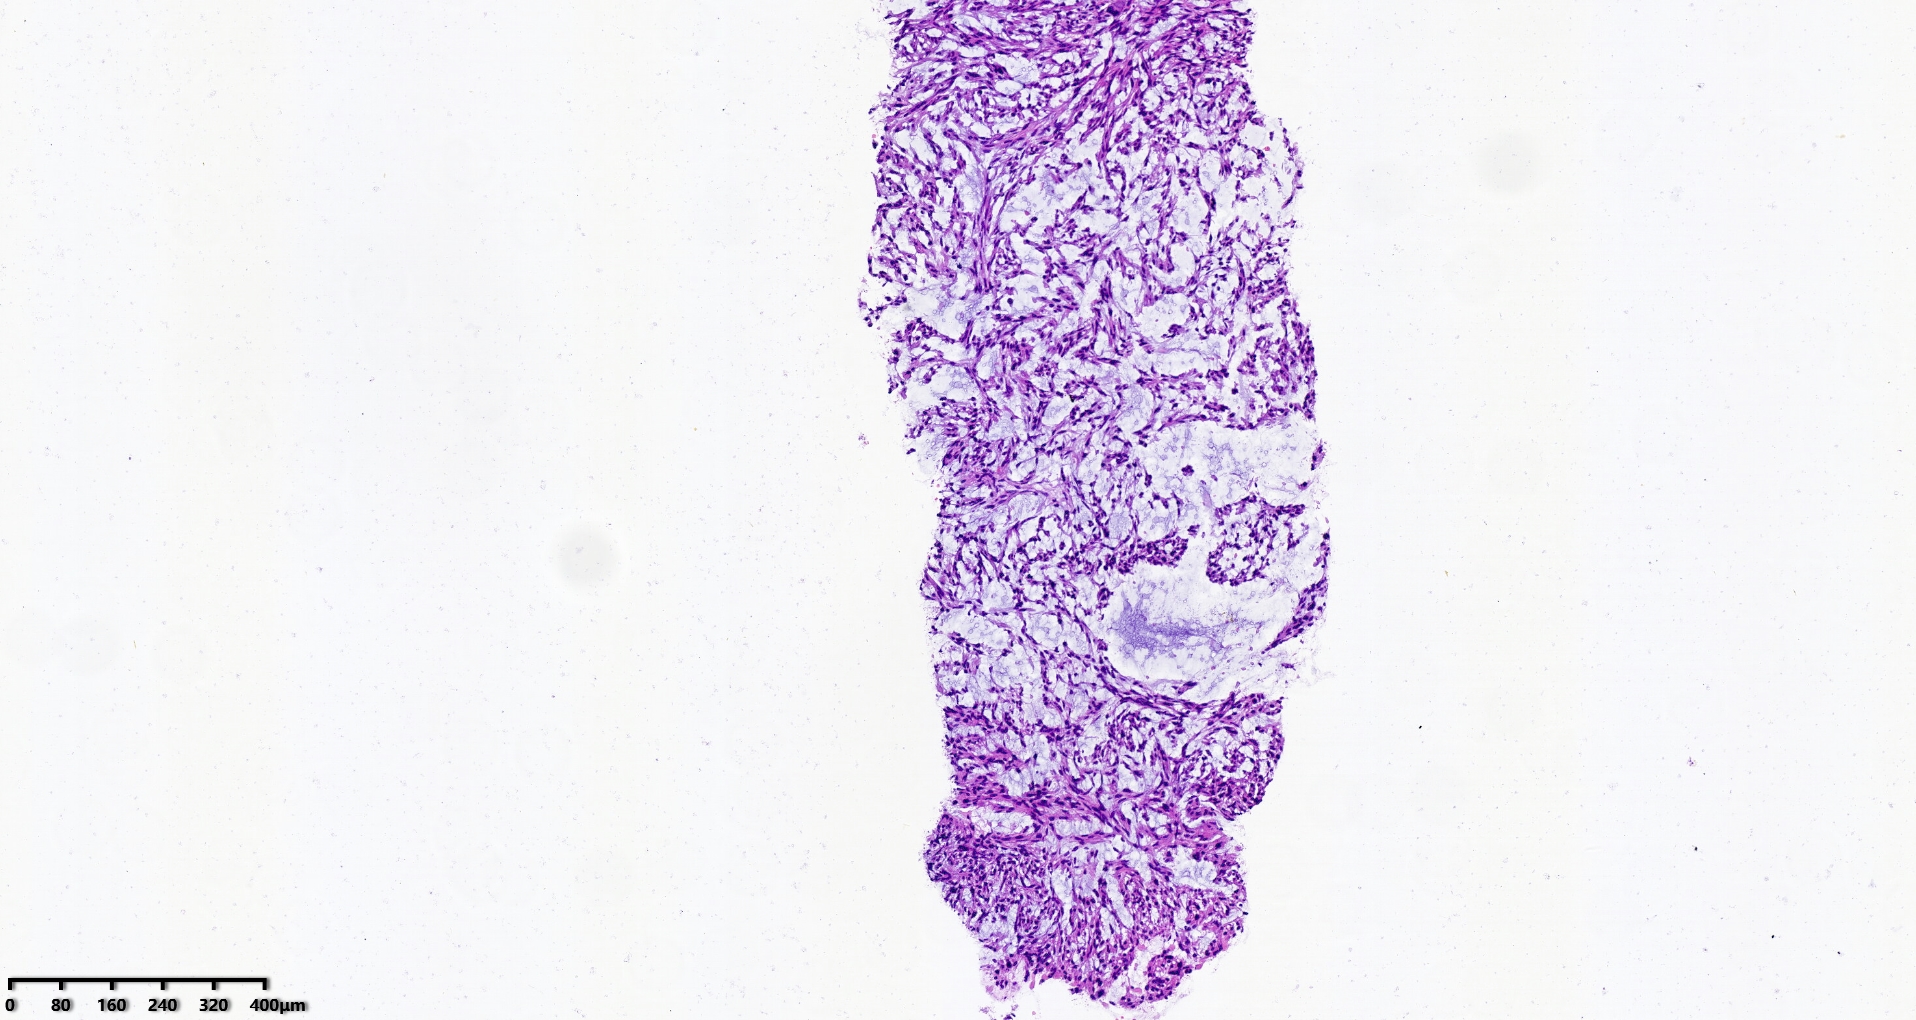

腹盆腔穿刺

腹盆腔肿物10.5×21.5cm大小

穿刺组织1.0×1.0cm

S100、CD34、MDM2、STAT6、CD117、CK均阴性

图1

考虑:深部软组织平滑肌肉瘤